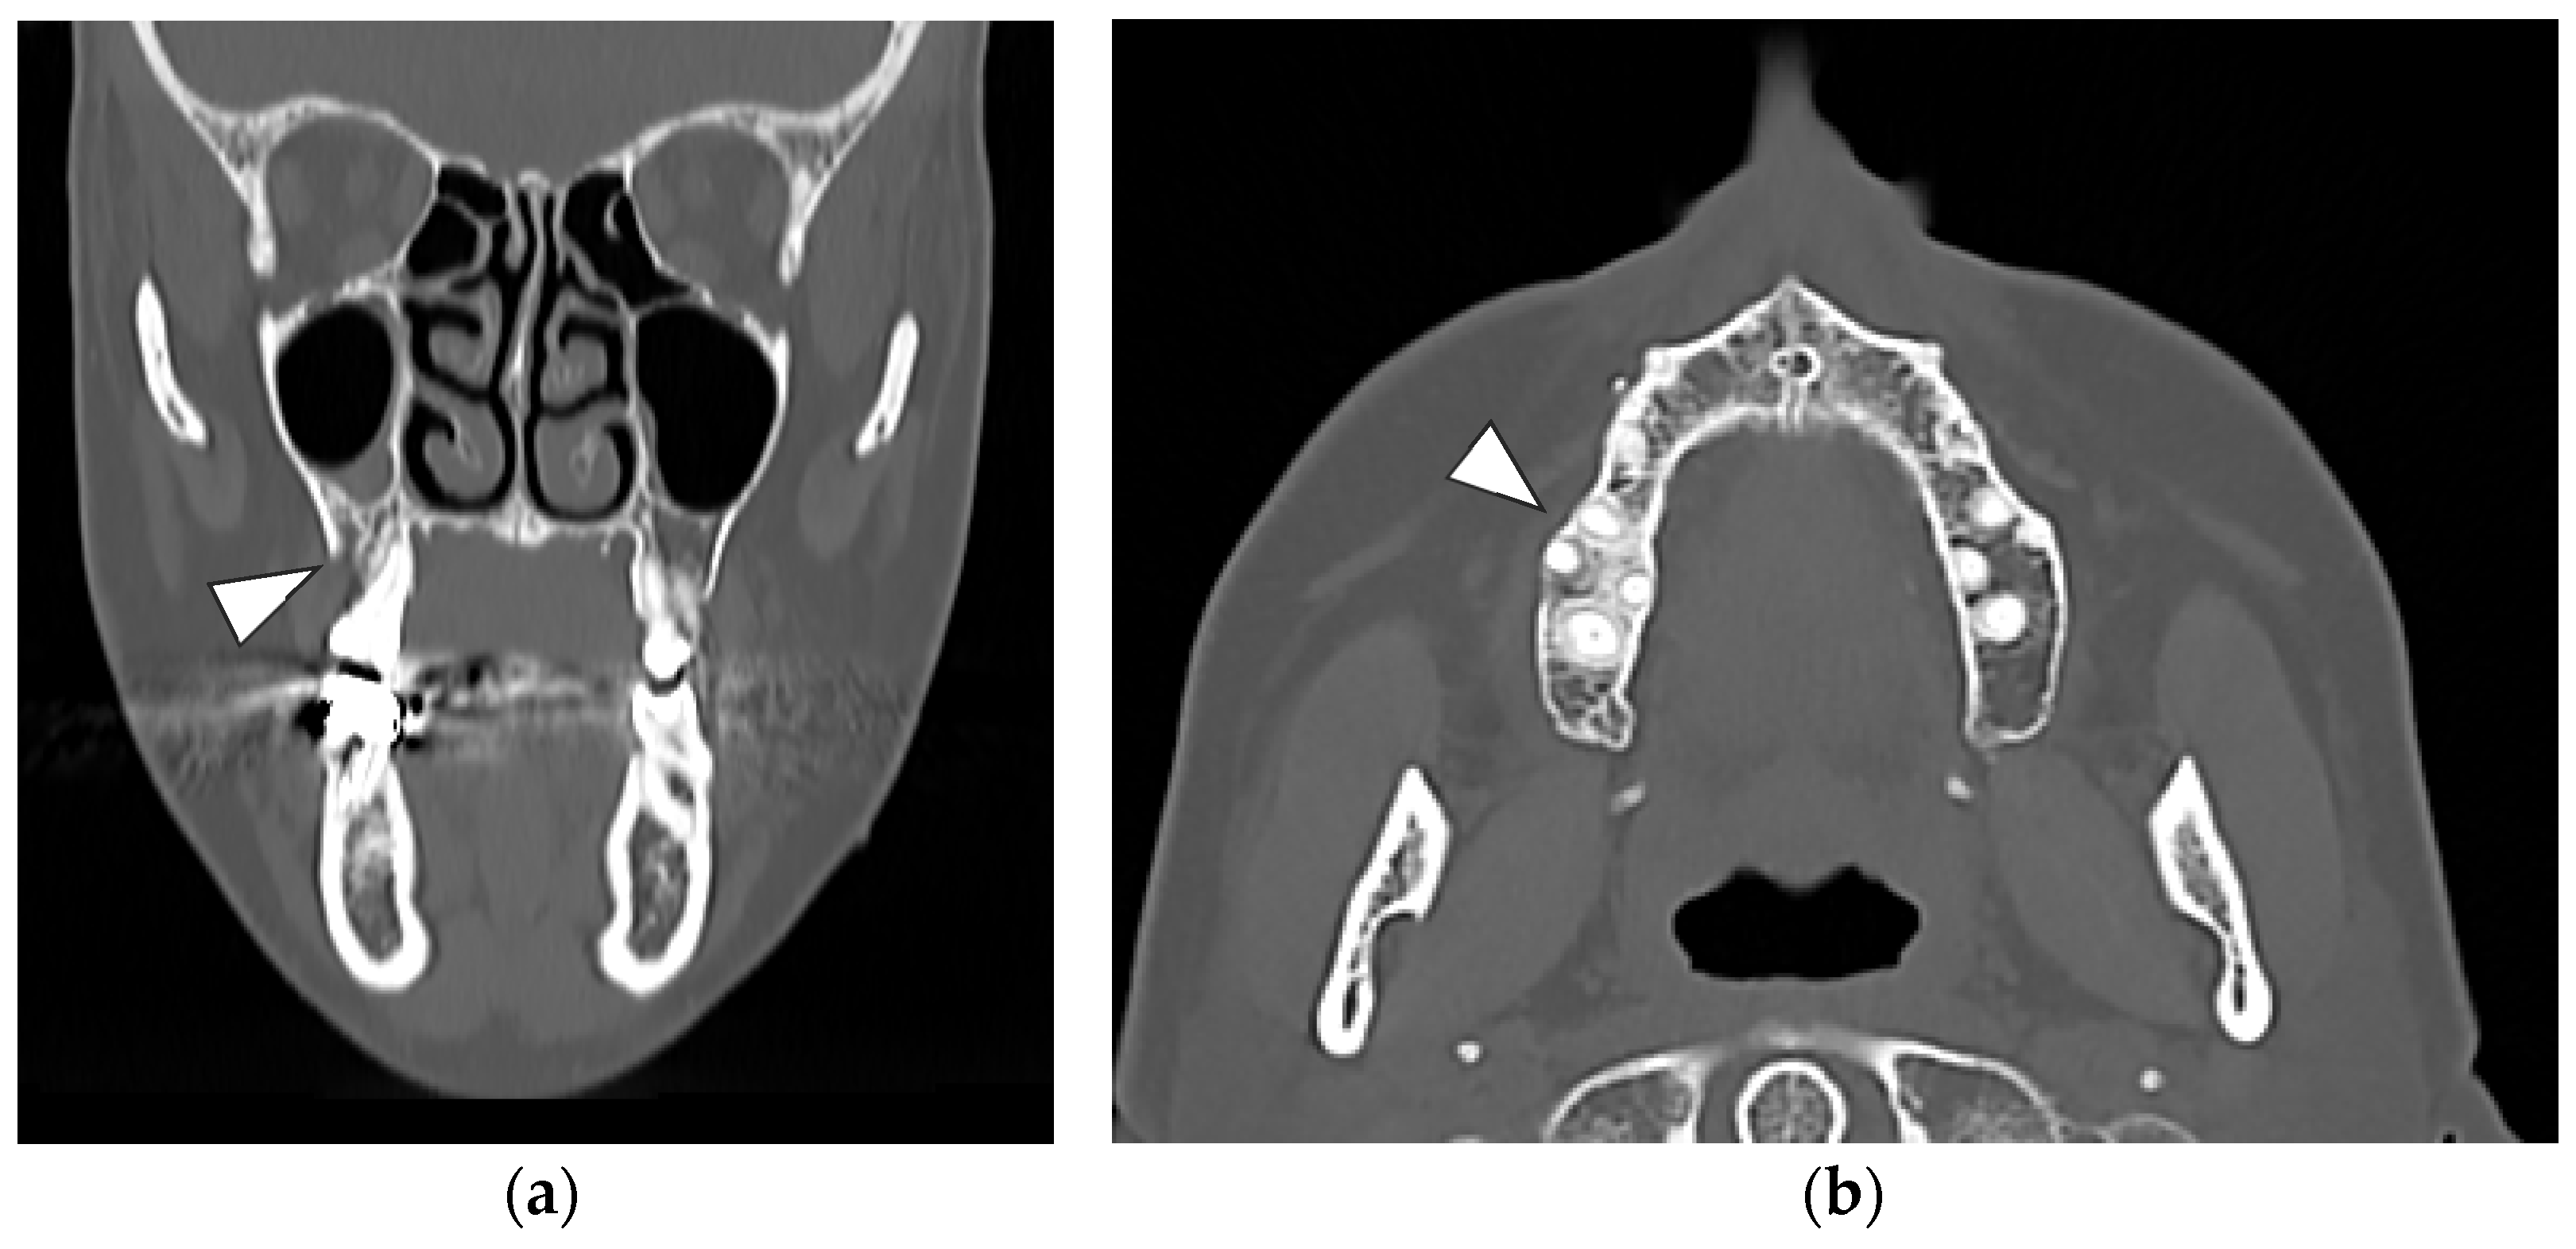

At computed tomography (CT), cortical erosion and widening of the periodontal space were detected. A focal increased trabecular bone density with loss of trabecular architecture was also detected around the alveolar bone. The radiological bone changes mainly involved the area of the first right molar but also extended to the alveolar bone of the second molar. The thickening of the maxillary sinus membrane was suggestive of a process involving the entire bone height (Figure 3a,b).

Figure 3. (a) Coronal CT view showing a cortical vestibular interruption at the site of the first right molar with an irregular trabecular pattern of alveolar bone (white arrowhead); (b) Axial CT view: a focal medullar bone sclerosis entirely surrounded the first molar roots with an extension at the area of the second molar associated with a thickening of the lamina dura (white arrowhead).